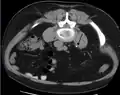

Otherwise a noncontrast helical CT scan with 5 millimeters (0.2 in) sections is the diagnostic method to use to detect kidney stones and confirm the diagnosis of kidney stone disease.[16][56][60][65][7] Near all stones are detectable on CT scans with the exception of those composed of certain drug residues in the urine,[58] such as from indinavir.

Renal ultrasonography can sometimes be useful, because it gives details about the presence of hydronephrosis, suggesting that the stone is blocking the outflow of urine.[58] Radiolucent stones, which do not appear on KUB, may show up on ultrasound imaging studies. Other advantages of renal ultrasonography include its low cost and absence of radiation exposure. Ultrasound imaging is useful for detecting stones in situations where X-rays or CT scans are discouraged, such as in children or pregnant women.[66] Despite these advantages, renal ultrasonography in 2009 was not considered a substitute for noncontrast helical CT scan in the initial diagnostic evaluation of urolithiasis.[65] The main reason for this is that, compared with CT, renal ultrasonography more often fails to detect small stones (especially ureteral stones) and other serious disorders that could be causing the symptoms.[14]

On the contrary, a 2014 study suggested that ultrasonography should be used as the initial diagnostic imaging test, with further imaging studies be performed at the discretion of the physician on the basis of clinical judgment, and using ultrasonography rather than CT as an initial diagnostic test results in less radiation exposure and equally good outcome.[67]